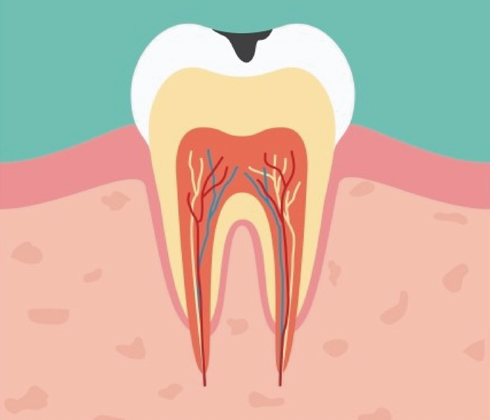

방치된 충치의 진행속도는 매우 빠릅니다.

단계가 진행 될 수록 치아 삭제량이 더 많아집니다.

단계가 진행 될 수록 치료 비용이 더 비싸집니다.

단계가 진행 될 수록 치료기간이 더 길어집니다.